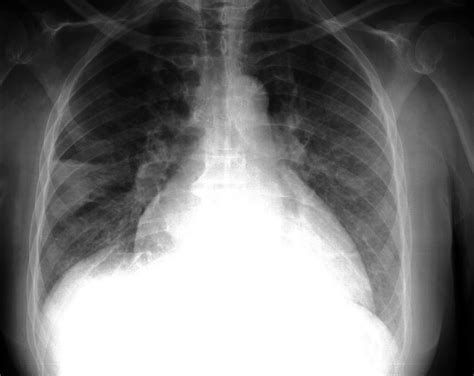

科学家发现肺癌干细胞代谢弱点 找到潜在靶向药物

在晚期非小细胞肺癌的治疗过程中,癌细胞产生治疗抵抗是到目前为止都无法解决的临床难题,越来越多的证据表明癌症干细胞是具有形成肿瘤并进行无限制自我更新能力的一群特殊细胞,传统治疗方法常常无法完全杀灭癌症干细胞,这也是导致治疗后复发和转移的关键原因。到目前为止科学家们对于癌症干细胞扩张过程中所需要的代谢途径仍了解不足,但对该问题的研究将有助于开发新的治疗手段。最近来自美国乔治城大学医学中心的研究人员发现了癌症干细胞的一个代谢弱点,并找到特异性靶向药物或可帮助提高传统治疗药物的效果。相关研究结果发表在国际学术期刊CellDeath&Differentiation上。

在这项研究中,研究人员发现肺癌干细胞依赖氧化磷酸化来产生细胞所需能量,维持细胞存活,并且这一过程依赖线粒体柠檬酸转运蛋白SLC25A1的活性。研究结果表明在癌症干细胞中SLC25A1在维持线粒体柠檬酸储备和氧化还原平衡方面发挥重要作用,抑制SLC25A1的活性会导致活性氧簇的积累因此抑制癌症干细胞的自我更新能力。

研究人员进一步发现在不同的病人来源肿瘤中,肿瘤对化疗药物顺铂和EGFR抑制剂治疗的抵抗作用需要通过SLC25A1介导的线粒体活性,诱导癌细胞表现出干性表型。他们找到一类新的SLC25A1特异性抑制剂,发现与顺铂或EGFR抑制剂联合使用能够产生更好的效果,重新恢复细胞和动物模型的抗肿瘤应答反应。

这些研究结果揭示了具有药物抗性的肺癌干细胞存在代谢弱点,具有重要临床其实,该研究还发现了一类新的SLC25A1抑制剂,证明通过药物阻断SLC25A1活性,结合传统的抗肿瘤药物能够产生更好的治疗效果。